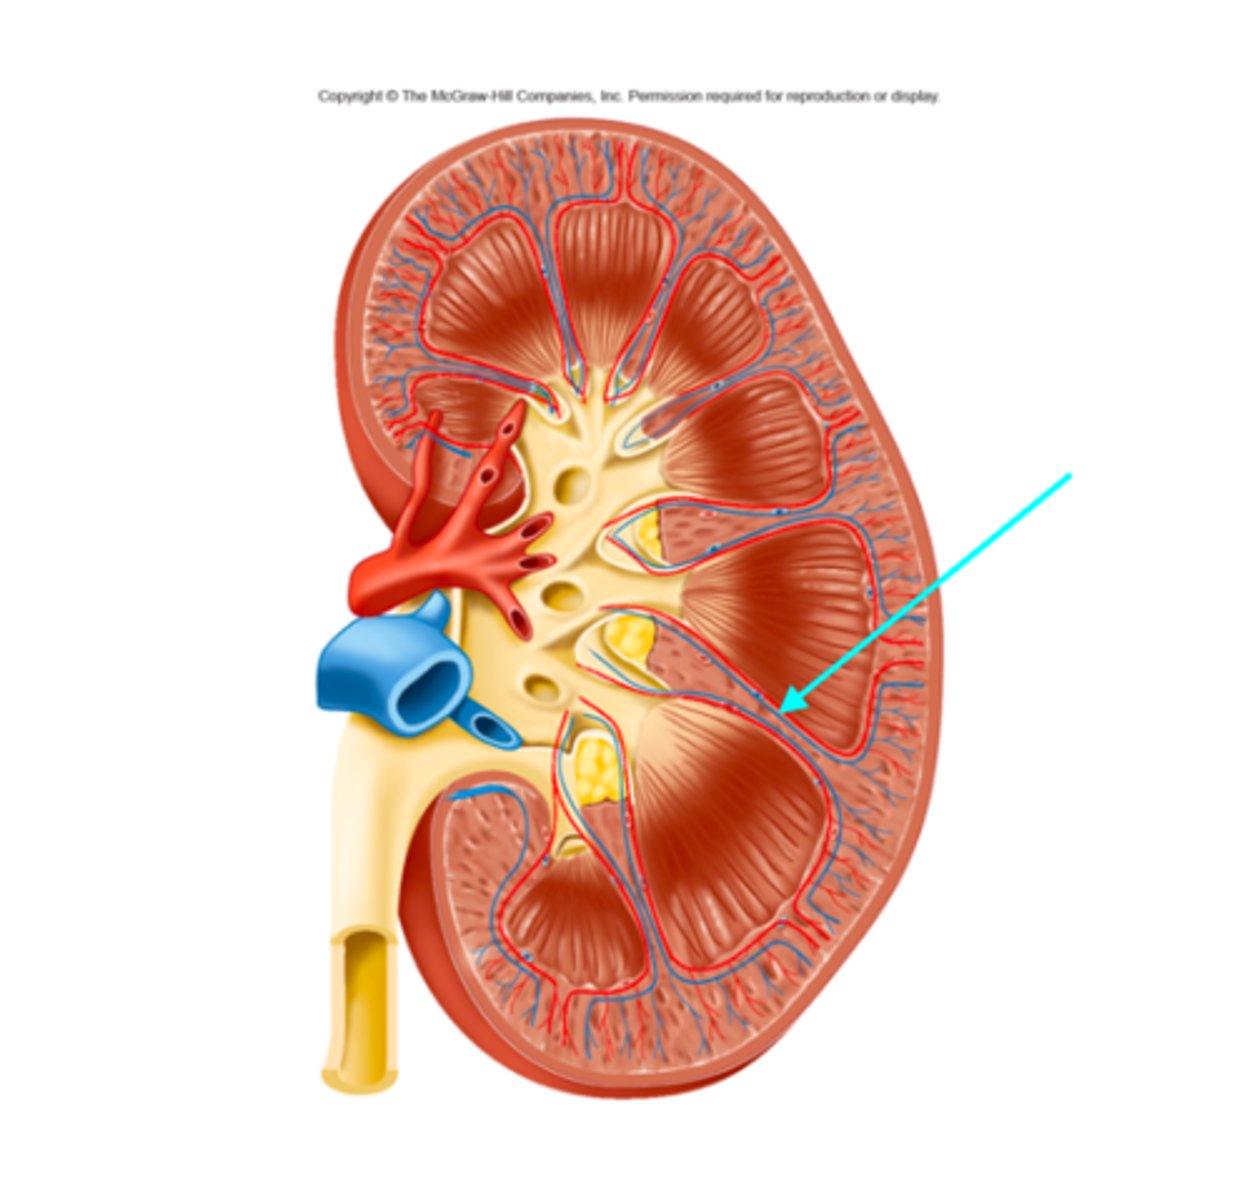

What structure of the kidneys is the blue arrow pointing at?

Cortical nephron

What structure of the kidneys is the blue arrow pointing at?